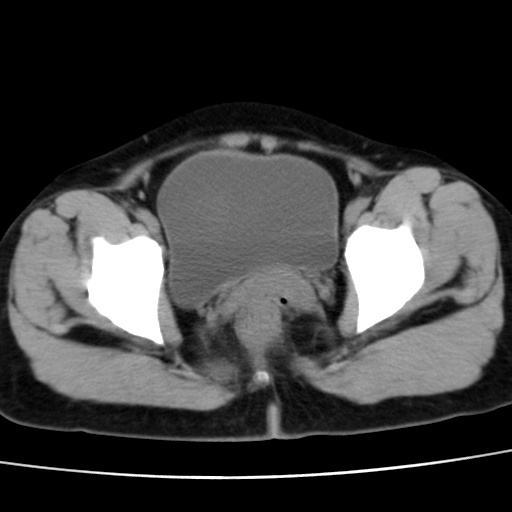

子宫多发肌瘤吗

多发性子宫肌瘤.

考虑多发子宫肌瘤,子宫直肠窝双囊性占位,另直肠周围脂肪密度增高,不知有何病史

支持考虑多发子宫肌瘤~!子宫直肠陷凹积液?

支持考虑多发子宫肌瘤~!子宫直肠陷凹积液!

子宫肌瘤,宫体部后方见液性密度影,是肠道还是子宫与直肠陷窝积液不好说,我觉得它的位置有点高

支持考虑多发子宫肌瘤!子宫直肠陷凹积液!

患者发热,而子宫直肠窝液性灶有明显边缘且局限且囊性,不除外为包裹性积液或脓肿

支持考虑多发子宫肌瘤,子宫直肠陷凹积液可能。

考虑多发子宫肌瘤

1)考虑子宫肌瘤可能性大。2)子宫后方囊性占位性病变,不排除卵巢囊肿可能。

考虑多发子宫肌瘤。子宫后方囊性占位性病变,不排除卵巢囊肿可能。